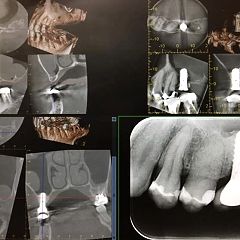

6最新インプラント症例を毎週アップしています実際のインプラント症例をとおして治療方法や問題点、治療費等最新の情報をお届けします。大船駅北口歯科 横浜市栄区-

24顎関節症から復活する歯科治療とは顎関節症から復活し一生健康で美しく生きることが可能となる歯列矯正と歯科治療とはどのようなものか?という疑問への実際の治療を用いた回答案を紹介するブログ-

初診→修復治療終了→歯列矯正終了→約10年経過 した歯医者さんの症例報告を、あなたはネット上で見たことがありますか? 矯正中のあなたの歯医者さんは、自分がやった症例の10年後の様子を画像で見せてくれたことがありますか?2022/07/29 14:32